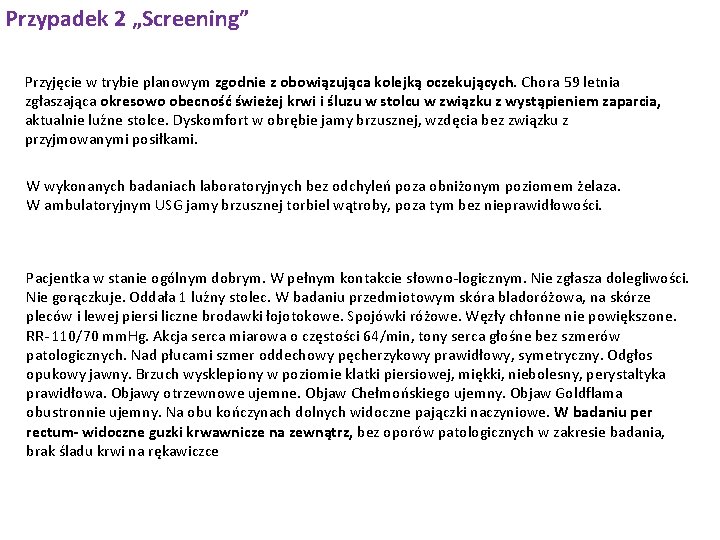

Przypadek 2 „Screening” Przyjęcie w trybie planowym zgodnie z obowiązująca kolejką oczekujących. Chora 59 letnia zgłaszająca okresowo obecność świeżej krwi i śluzu w stolcu w związku z wystąpieniem zaparcia, aktualnie luźne stolce. Dyskomfort w obrębie jamy brzusznej, wzdęcia bez związku z przyjmowanymi posiłkami. W wykonanych badaniach laboratoryjnych bez odchyleń poza obniżonym poziomem żelaza. W ambulatoryjnym USG jamy brzusznej torbiel wątroby, poza tym bez nieprawidłowości. Pacjentka w stanie ogólnym dobrym. W pełnym kontakcie słowno-logicznym. Nie zgłasza dolegliwości. Nie gorączkuje. Oddała 1 luźny stolec. W badaniu przedmiotowym skóra bladoróżowa, na skórze pleców i lewej piersi liczne brodawki łojotokowe. Spojówki różowe. Węzły chłonne nie powiększone. RR- 110/70 mm. Hg. Akcja serca miarowa o częstości 64/min, tony serca głośne bez szmerów patologicznych. Nad płucami szmer oddechowy pęcherzykowy prawidłowy, symetryczny. Odgłos opukowy jawny. Brzuch wysklepiony w poziomie klatki piersiowej, miękki, niebolesny, perystaltyka prawidłowa. Objawy otrzewnowe ujemne. Objaw Chełmońskiego ujemny. Objaw Goldflama obustronnie ujemny. Na obu kończynach dolnych widoczne pajączki naczyniowe. W badaniu per rectum- widoczne guzki krwawnicze na zewnątrz, bez oporów patologicznych w zakresie badania, brak śladu krwi na rękawiczce